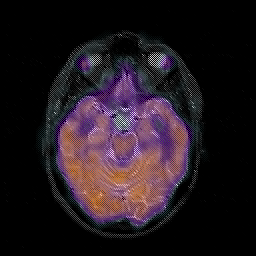

Glioblastoma multiforme overlay -- Slice #21

[Home][Help][Clinical][Tour 1][Tour 2][Tour 3] Slice 21